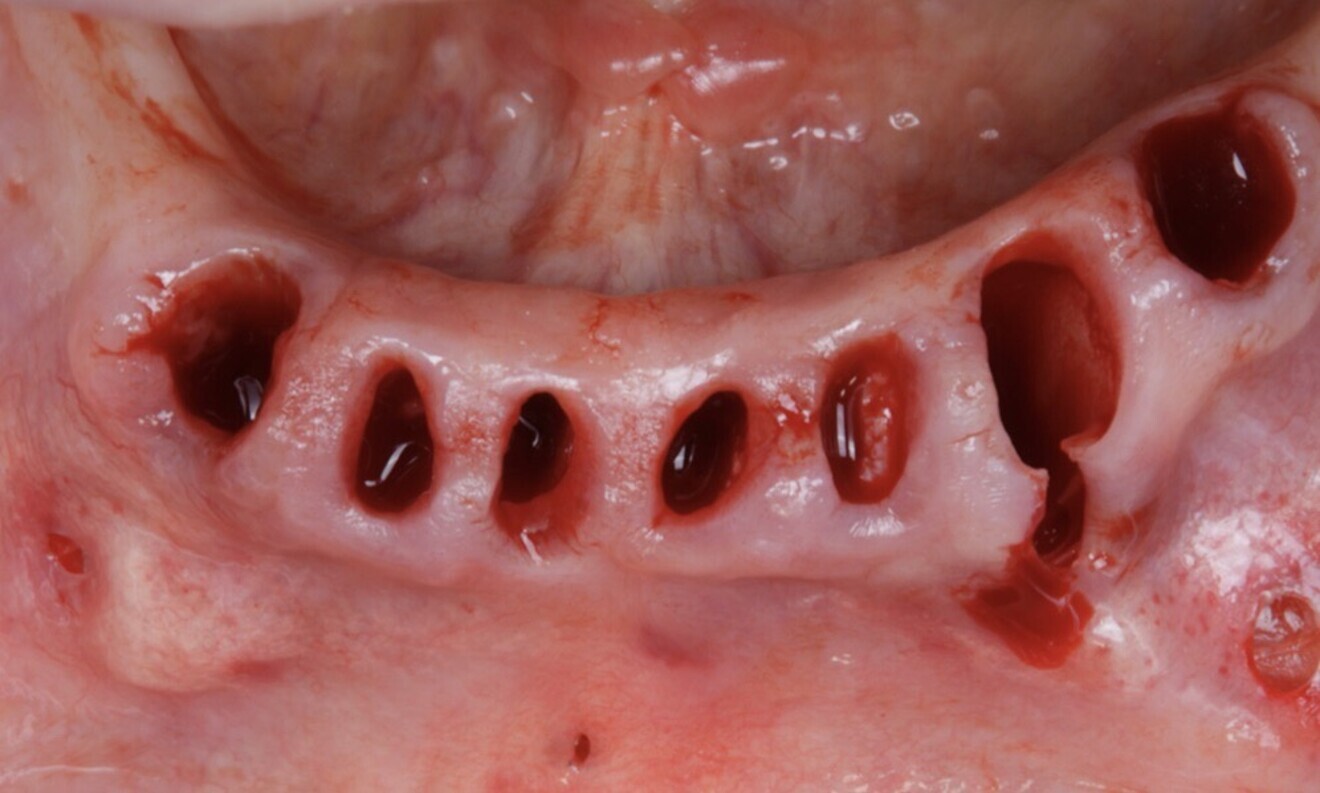

For the mandibular arch, the first surgical guide was checked for proper fit (Fig. 29). The surgical guide, supported by the teeth, was placed, and anchor pins were inserted (Figs. 30 & 31). After this, the guide was removed, and the hopeless teeth were atraumatically extracted (Figs. 32 & 33).

Figs. 32 & 33: The hopeless teeth were atraumatically extracted.

After tooth extraction, a full-thickness mucoperiosteal flap was created to provide adequate access to the surgical site (Figs. 34 & 35). A buccal and lingual vertical releasing incision was made to ensure tension-free closure. The incision extended beyond the area of planned bone reduction to facilitate proper flap mobilisation and ensure good coverage for the healing process.